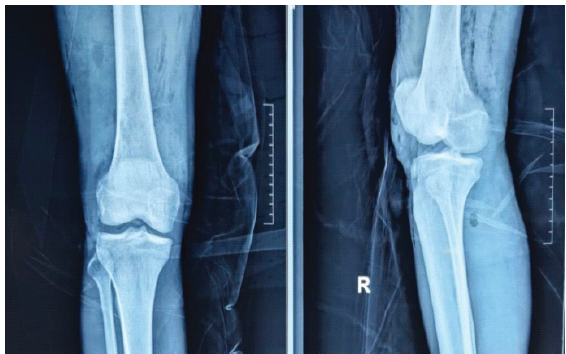

After taking due informed consent, the patient was taken to the operation theatre after 3 h of his arrival. He was placed in a supine position on the operating table. General anesthesia was administered and airway secured. A tourniquet was used at an appropriate pressure to aid in the procedure. The vascular surgery team was informed to be in standby mode. Removal of blade from the ankle was attempted first. Incisions were given at the entry and exit wounds, and a thorough wash was given. The metallic blade was removed with a single pull. Twists and turns were avoided to prevent any iatrogenic damage to the surrounding structures [4]. The area was thoroughly washed once more with normal saline and diluted betadine. Incisions were then carefully made without deep dissection at the entry and exit wounds in the knee. A light mallet was used to gently strike at the anterior aspect of the metallic blade in a controlled manner. The rod was then removed with a single pull. Along with the blade, the entire portion of the torn clothing was removed. Careful debridement was then done at both sites (knee and ankle) along with copious irrigation. Complete removal of the objects was confirmed clinically and through fluoroscopy. Gentle examination under anesthesia (Joint stability tests) was then performed, which suggested ligament injuries in both sites. The tourniquet was then deflated to check for any inadvertent arterial injury. SpO2 of the limb was >94%. Once the absence of arterial injury was confirmed, the wound was closed in layers. An above-knee anterior slab was put for adding stability of the joints and injured soft tissues. The post-operative radiograph documented the absence of any foreign bodies. Post-operatively an magnetic resonance imaging (MRI) was also done, which confirmed lateral meniscus and lateral collateral ligament injuries, anterior talofibular, calcaneofibular and tibiotalar ligaments in both the knee and the ankle, respectively. Absence of any retained clothing was also confirmed in the MRI. His post-operative hospital stay was mostly uneventful except for a superficial wound infection at the popliteal entry wound that eventually healed with IV antibiotics, single debridement, and regular dressings. The sutures were removed at the end of the 2nd week. The patient was then discharged in satisfactory clinical condition with the explanation that he may eventually require knee and ankle arthroscopy and reconstruction of some of the critically torn ligaments of the knee and ankle joint if these fail to heal satisfactorily (Fig. 6, 7, 8, 9, 10).

Figure 9: Post-operative anterior – posterior and lateral check radiograph of the right knee.